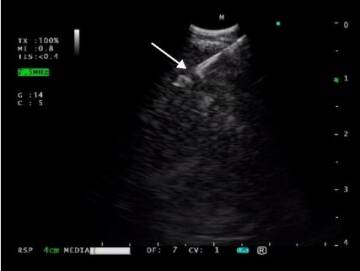

Celem pracy polskich specjalistów była ocena skuteczności EBUS/EUS -b-NA przy użyciu histologicznych igieł o średnicy 25 w szczegółowej diagnostyce chorych z zaawansowanym stadium raka płuc.